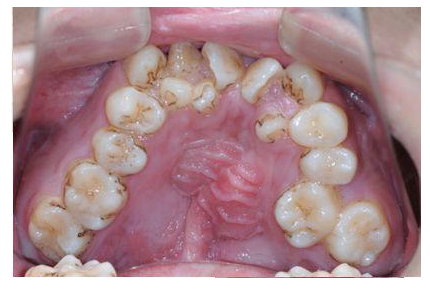

全民矫牙公益行动青少年矫牙误区有哪些

误区1:牙齿不齐只影响美观并无大碍

牙齿畸形不仅影响美观,还可能会影响口腔功能的正常发挥,如咀嚼功能、发音功能、呼吸功能,甚至由于牙齿排列不齐,难以清洁导致蛀牙等。

对于青少年阶段的牙齿畸形问题,应该及时选择适宜的早期矫治,才能更好地促进儿童面部和牙弓的发育,为现有牙齿和即将萌出的恒牙创造空间。